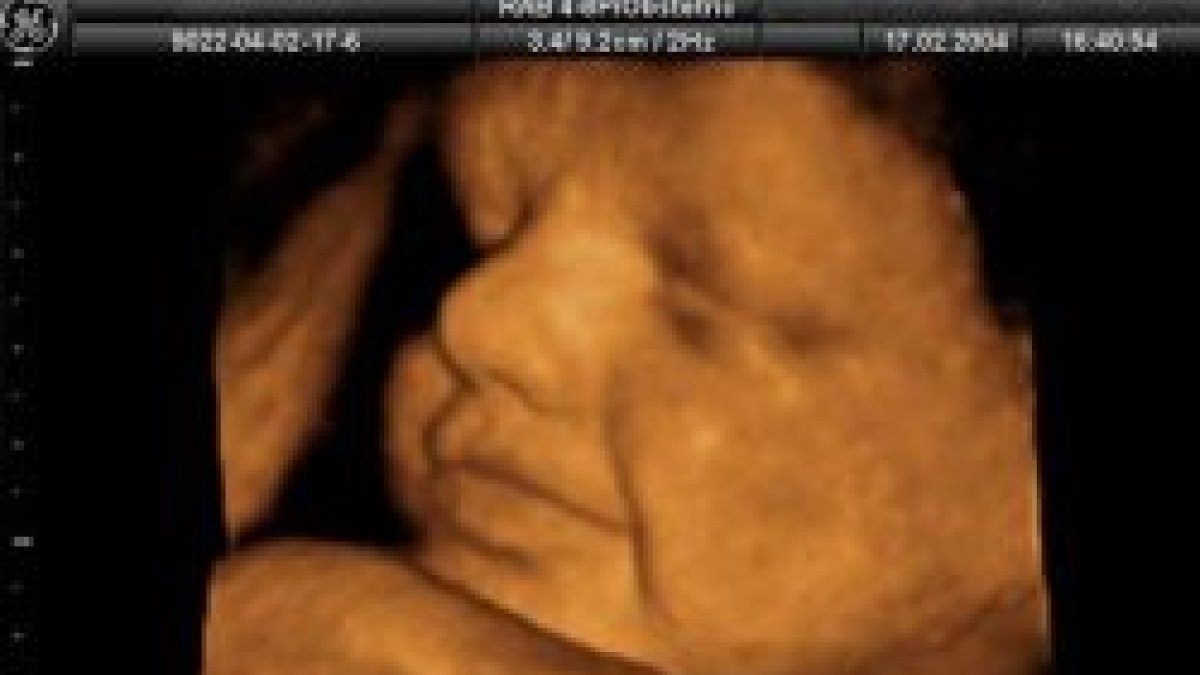

(LD/EP) La tasa de interrupciones voluntarias, es decir, el número de mujeres que han interrumpido el embarazo por cada 1.000 en edad fértil (15-44 años), se situó en 2007 en el 11.49 frente al 10.62 del año anterior. El 88,15% de las interrupciones se realizaron en gestaciones de menos de 12 semanas -el 62,84 por ciento en gestaciones de ocho o menos de dos semanas y el 25.31% entre las nueve y las 12 semanas--, datos que han experimentado un leve aumento respecto a 2006, cuando el 87,94% de las interrupciones se realizaron en gestaciones de menos de 12 semanas.